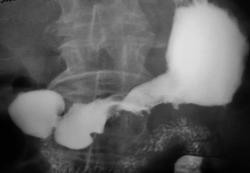

Пациент направлен на рентгенологическое исследование врачом терапевтом. Пациент предъявляет жалобы на боли в эпигастральной области. За последний год значительно похудел.

Иллюстрации представлены по мере заполнения желудка взвесью сернокислого бария.

Ваше мнение коллеги по поводу "образования" в луковице 12-ти перстной кишки, помеченного жёлтыми стрелками, и по поводу "образования" в желудке, помеченного красными стрелками.

Полностью согласен, что данном наблюдении мы сталкиваемся с инфильтративным тотальным навообразованием желудка, однако протяженность поражения заставляет включить в ряд дифференциальной диагностики еще и лимфому.